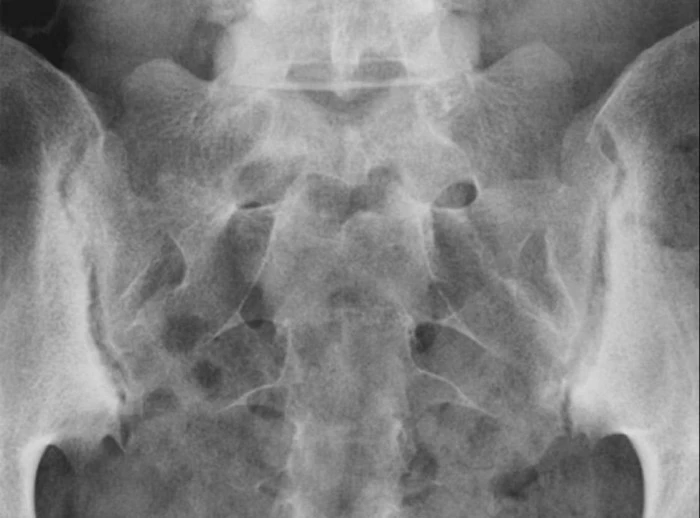

На фото изображен двусторонний сакроилиит у пациента с анкилозирующим спондилитом.